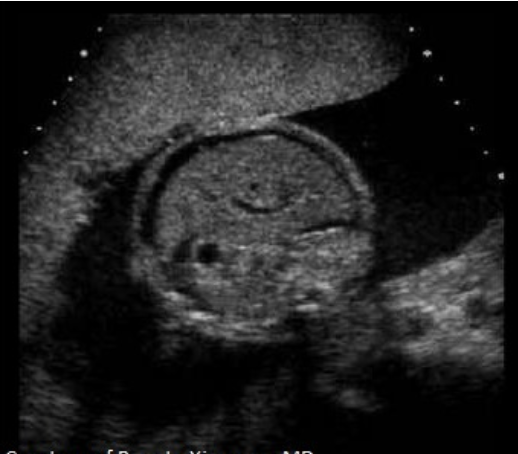

this is frog eyes aka anencephaly

d) AFP